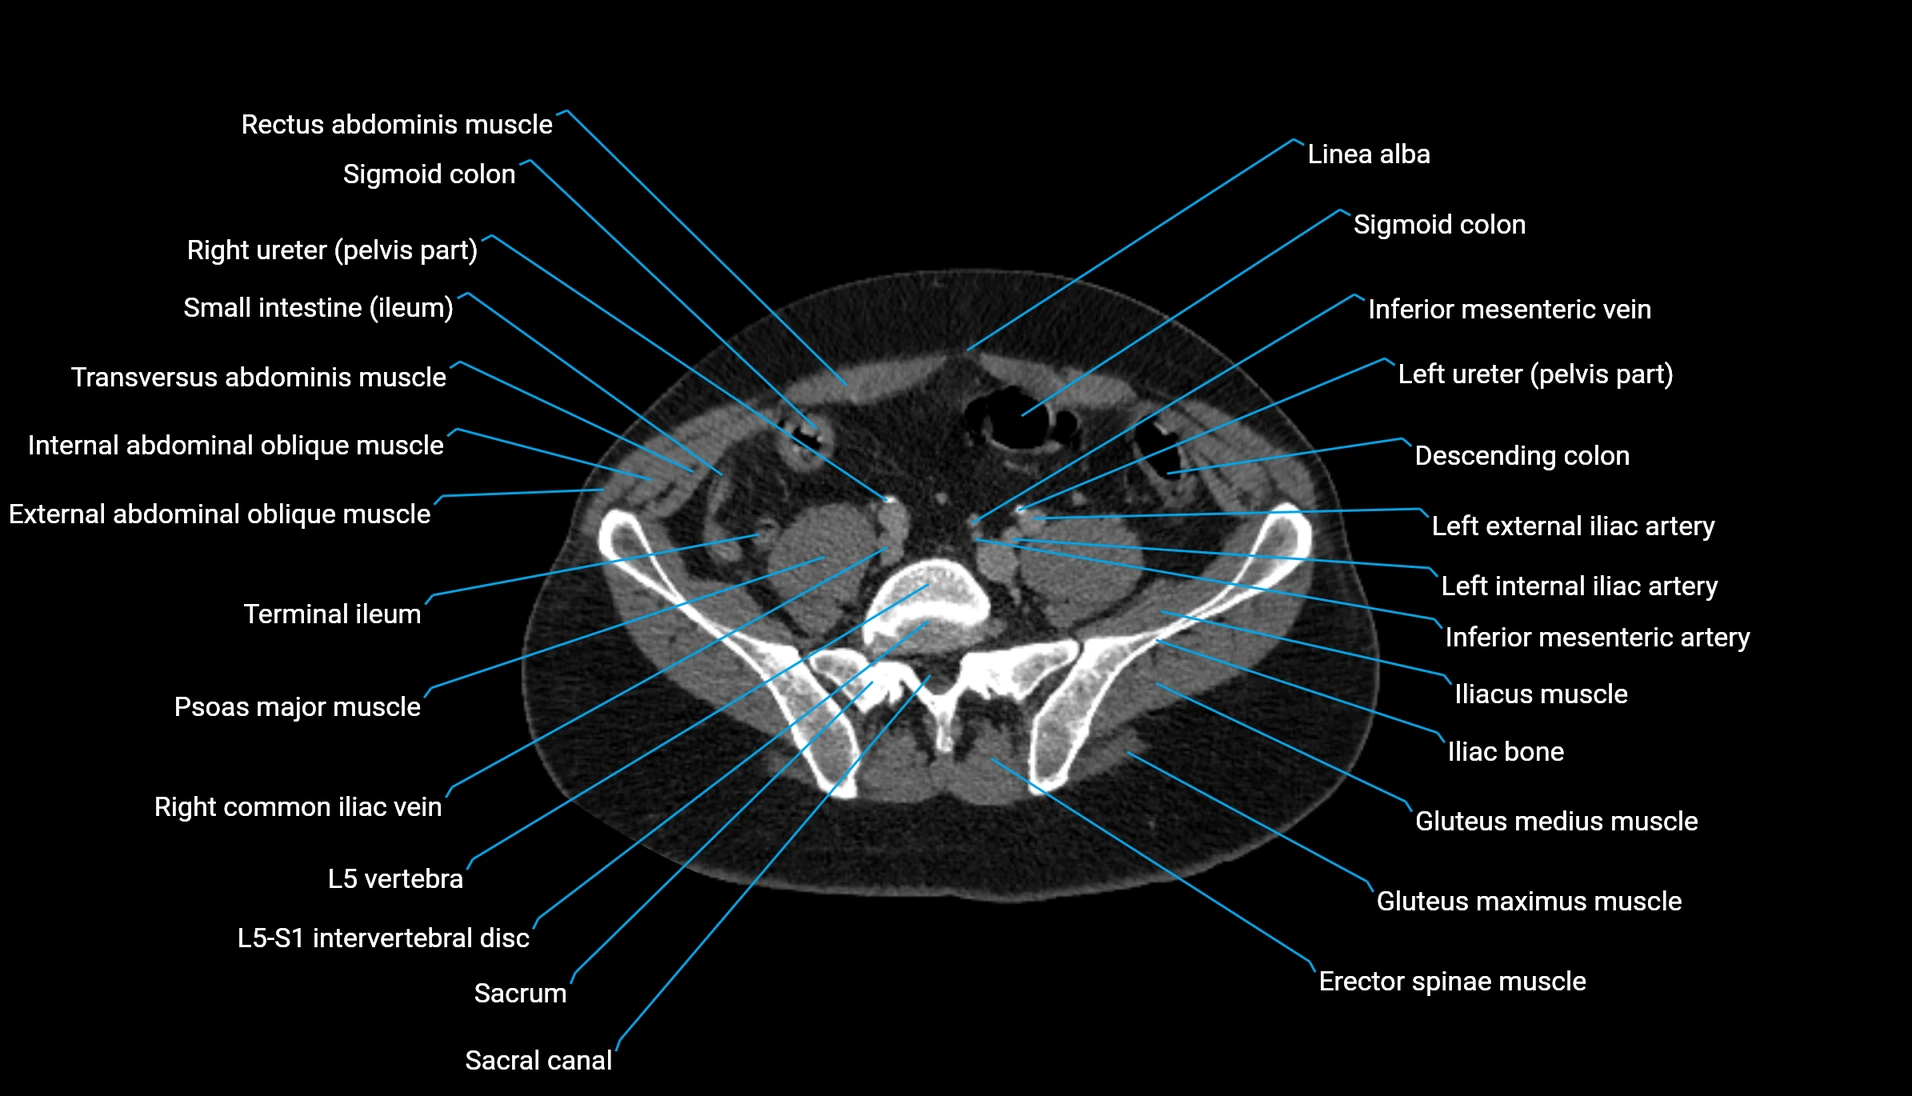

CT Appearance

Non-contrast CT:

-

Demonstrates cortical bone of acetabular rim in excellent detail

Detects fractures, dysplasia, retroversion, or bony overcoverage (pincer impingement)

3D reconstructions used in preoperative hip surgery planning

CT VRT 3D image

CT image